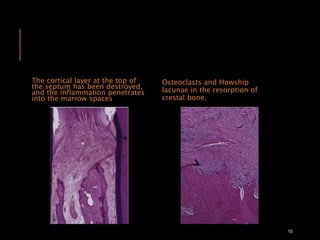

The cortical layer at the top of

the septum has been destroyed,

and the inflammation penetrates

into the marrow spaces

Osteoclasts and Howship

lacunae in the resorption of

crestal bone.